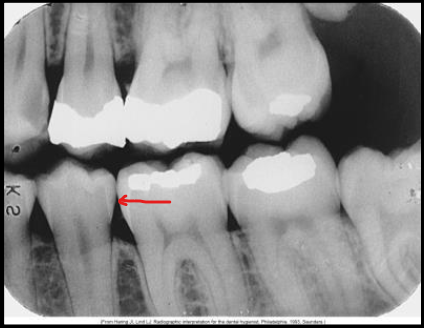

What class of interproximal caries is this?

Class 1 - incipient lesion